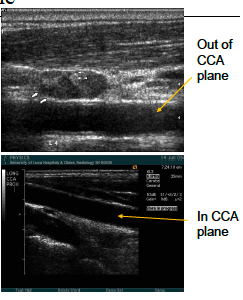

what are the arrows pointed to? what approach is being used?

trans CCA prox

what are teh arrows pointing to here? what image is being taken?

trans CCA mid

If the vessel has “echoes” in it, you maybe out of the vessel plane and pickup up the wall.

You must “______” the transducer back into the vessel.

tip *(do not “turn)